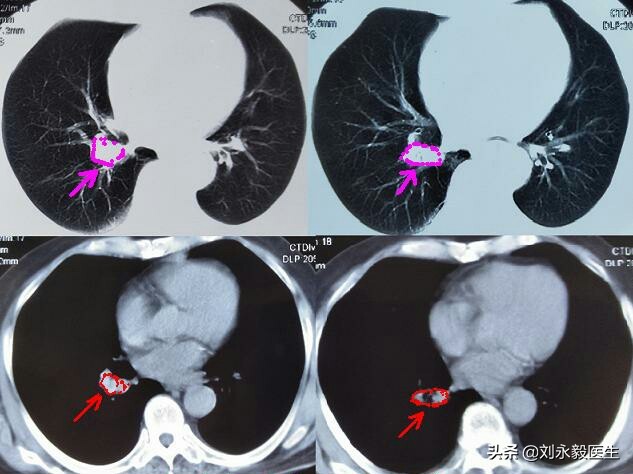

上图是某患者初诊肺癌时的胸部CT,肿瘤不大,如果此时手术,生存时间可能要好很多,很遗憾,采取了“中药化疗”,2018年11月胸闷气短,检查CT发现气管隆突处肿瘤堵塞主支气管,如下CT图。